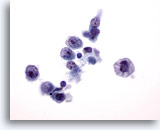

Lymph node FNA, reactive lymphoid hyperplasia. A FNA of a lymph node may yield small irregular clusters of macrophages and lymphocytes. These should not be misinterpreted as an epithelial neoplasm. There are two such clusters here along with many other small round cells of varying sizes. 20x

Lymph node FNA, reactive lymphoid hyperplasia.

A FNA of a lymph node may yield small irregular clusters of macrophages and lymphocytes. These should not be misinterpreted as an epithelial neoplasm. There are two such clusters here along with many other small round cells of varying sizes.

20x

Figure 65

Lymph node FNA, reactive.

One cluster contains macrophages with intracytoplasmic pigment, so called tingible body macrophages. 40x

Lymph node FNA, reactive.

One cluster contains macrophages with intracytoplasmic pigment, so called tingible body macrophages.

40x

Figure 66

Lymph node FNA, reactive.

The three tingible body macrophages are shown at high magnification. 60x

Lymph node FNA, reactive.

The three tingible body macrophages are shown at high magnification.

60x

Figure 67

Lymph node FNA, reactive. There is a range of maturation of lymphocytes seen. Small mature lymphocytes, slightly larger and very large lymphocytes are present. A mitotic nucleus can be seen. Tingible body macrophages and a range of maturation make the diagnosis of reactive hyperplasia. 60x

Lymph node FNA, reactive.

There is a range of maturation of lymphocytes seen. Small mature lymphocytes, slightly larger and very large lymphocytes are present. A mitotic nucleus can be seen. Tingible body macrophages and a range of maturation make the diagnosis of reactive hyperplasia.

60x